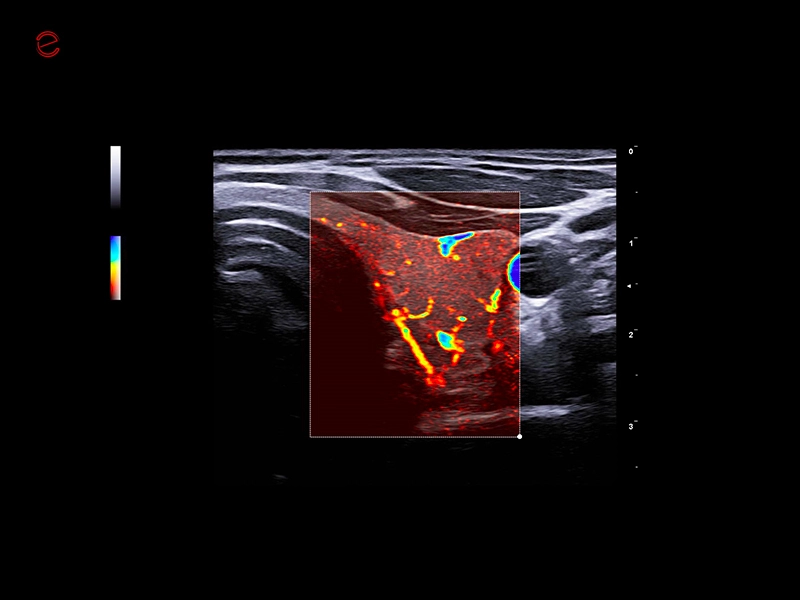

MyLab™9 Platform - Hemodynamics analysis using microV on kidney

MyLab™9 Platform - Hemodynamics analysis using microV on kidney